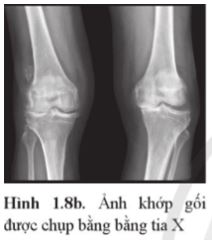

Giải thích vì sao có vùng màu sẫm, vùng màu sáng ở ảnh chụp khớp gối bằng tia X trong Hình 1.8b.

Lời giải:

Khi xuyên qua các mô mềm, chùm tia X ít bị giảm cường độ nên trên phim sau khi tráng, vùng tương ứng với các mô mềm có màu sẫm. Vì xương làm giảm cường độ chùm tia X nhiều hơn so với các mô mềm nên trên phim sau khi tráng vùng tương ứng với vị trí của xương có màu sáng hơn.